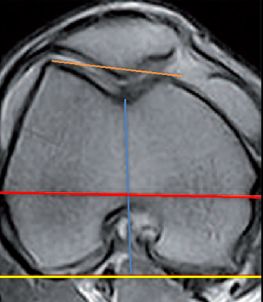

For the natural knee it is well known that the femur flexion axis represents a very complex helical structure due to the asymmetric bones, menisci and both cruciate ligaments. For TKA surgery the transepicondylar axis (TEA) represents the best compromise for the knee flexion axis [2,6]. The problem with the TEA is, that intraoperative identification is difficult, and several studies have shown wide inter- and intraobserver variability [8]. Therefore, many other different landmarks had been described to reduce this problem and increase the accuracy to identify the TEA [2,7] (Fig 9). Most of TKA instruments still use the most prominent point of both posterior condyles (posterior condylar axis) as reproducible landmarks to set femur rotation.

For many decades standardized 3° ER were used to bring the femur component parallel to the TEA by referencing to the posterior condylar axis. The new 3-D mega data clearly demonstrated that in knees planned for TKA surgery a wide range of internal rotation (minus 3 ER to 11° IR) of the posterior condylar axis to the TEA exists (Fig 10) [27,31,32].

For valgus knees it was well known that due to the possible hypoplastic lateral condyle the posterior condylar axis might be more than 3° of IR and many surgeons routinely used 5° ER to the TEA in valgus knees. A wide range from 3° to 12° of IR of the posterior condylar axis to the TEA could be shown with the new 3-D mega data for valgus knees also [32]. For varus knees it was long assumed that 3° of ER will fit for rotational alignment. Now we know that even in varus knees axial plane femur deformities are possible and show a wide range from 3° of ER (worn out posterior medial condyle) to 9° of IR (hyperplastic medial condyle) from the posterior condylar axis to the TEA (Fig 11) [32]. 32 % of femur needs more than 3-5° ER (6-11), whereas 10 % less than 3° ER (IR 3 to ER 2°) [31].